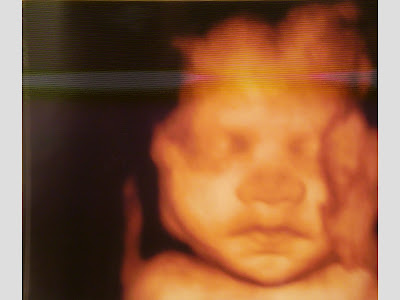

Et la Pomme en personne: